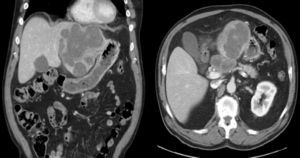

Abdominal ultrasound showed a large solid mass that distended and deformed the left hepatic lobe. CT images were compatible with a polylobed hepatic neoformation, which was probably primary and had uncertain extension to the body of the pancreas and celiac trunk (Fig. 1).

During surgery, a tumor was observed in segments II–III, and a 6cm lymph-node conglomerate was seen in the celiac trunk with extension to the body of the pancreas. No extrahepatic mass was observed.